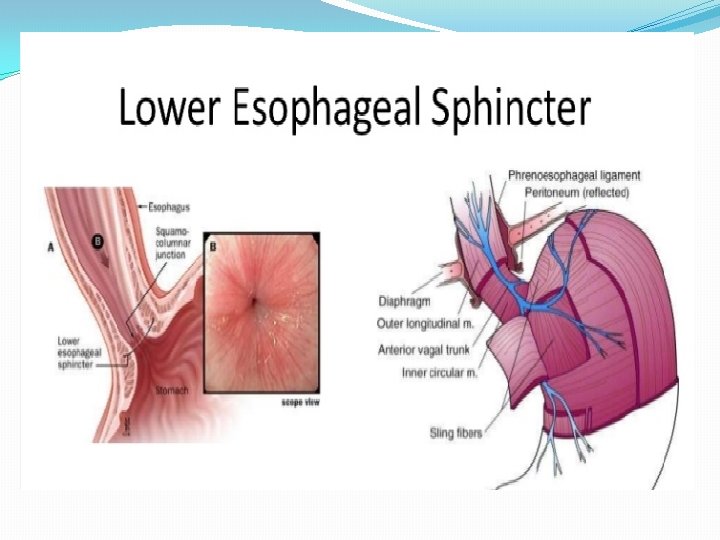

Pathophysiology Antireflux barrier: *lower esophageal sphincter (LES) *the crura of the diaphragm *gastroesophageal junction anatomy

The mechanisms involved in the pathogenesis of GERD are multiple and include: 1. impaired LES resting tone 2. increased number of transient LES relaxations (TLESR) 3. Gastric distention (delayed gastric emptying, large fatty meals) can significantly increase the rate of transient LES relaxations) 4. hiatal hernia (promoting lower oesophageal sphincter dysfunction)